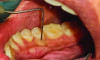

The MGJ was delineated by the visual method and the roll method following clinical examination in dental chairs appropriately equipped. Visual assessment relies on identifying the color difference between the gingiva and alveolar mucosa. The mucosa beyond the MGJ typically appears darker red compared to the AG, helping to demarcate the MGJ. The rolling probe method entails pushing the neighboring alveolar mucosa coronally with the blunt end of a probe. It is a functional assessment method that aids in determining the boundary between gingiva and movable mucosa.10 The probing sulcus depth was subtracted from the measured KG width at the mid-lingual aspect of each tooth to determine the width of AG, and all fractional measurements were rounded off to the nearest whole number of millimeters (Figure 1 through Figure 3).

Fig 1 through Fig 3. Measurements of lingual attached gingiva: Fig 1 = identifying the MGJ.

Figure 1

Fig 2 = sulcus depth measurement.

Figure 2